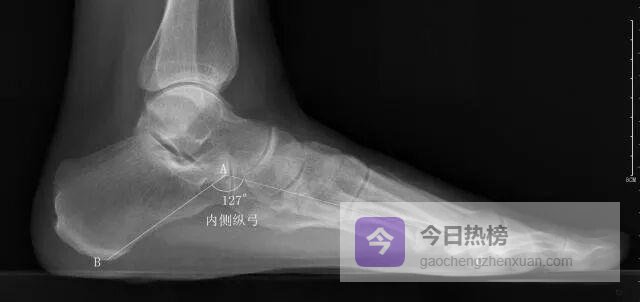

4.2 ◆ 四大角度测量法 4.2.1 ◆ 内侧纵弓角以距骨头最低点为原点,向跟骨最低点与第1跖骨头最低点各引一条水平线, 测量两线夹角。